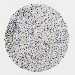

GLIOMA - Protein expressioni

A mouse-over function shows sample information and annotation data. Click on an image to view it in a full screen mode. Samples can be filtered based on level of antibody staining by selecting one or several of the following categories: high, medium, low and not detected. The assay and annotation is described here.

Note that samples used for immunohistochemistry by the Human Protein Atlas do not correspond to samples in the TCGA dataset.

Antibody stainingi

Antibody staining in the annotated cell types in the current human tissue is reported as not detected, low, medium, or high, based on conventional immunohistochemistry profiling in selected tissues. This score is based on the combination of the staining intensity and fraction of stained cells.

Each image is clickable and will lead to virtual microscopy that enables deeper exploration of all samples and also displays staining intensity scores, fraction scores and subcellular localization as well as patient and tissue information for each sample.

Antibody HPA011155

Staining

High

Medium

Low

Not detected

Intensity

Strong

Moderate

Weak

Negative

Quantity

>75%

75%-25%

<25%

None

Location

Nuclear

Cytoplasmic/membranous

Cytoplasmic/membranous,nuclear

Glioma, malignant, High grade

Glioma, malignant, Low grade